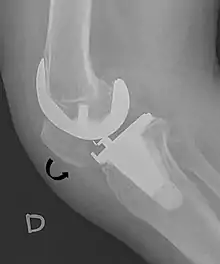

Patella baja.[4]

A patella baja is a low-riding patella. A long-standing patella baja may result in extensor dysfunction.[5]

Insall-Salvati ratio (A divided by B).[6]

The Insall-Salvati ratio helps to indicate patella baja on lateral X-rays, and is calculated as the patellar tendon length divided by the patellar bone length. An Insall-Salvati ratio of < 0.8 indicates patella baja.[6]